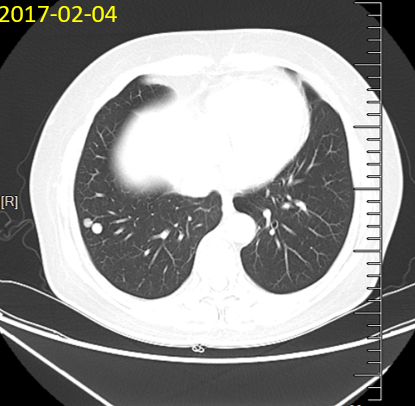

2017-02-04 胸腹盆CT提示双肺多发转移灶,余未见明显转移征象

2017-03-10行化疗,方案为:奥沙利铂200mg iv d1+卡培他滨1.5g Po Bid d1-14,21d一周期。2017-04-07、 2017-04-27、2017-05-23、2017-06-23、2017-07-19行化疗联合靶向,方案为:奥沙利铂200mg iv d1+卡培他滨1.5g Po Bid d1-14+贝伐珠单抗 480mg iv d1,21d一周期。